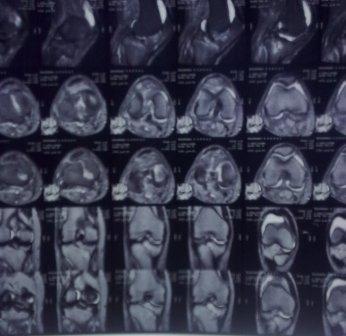

Сегодня обратился больной 35л. Травму получил 3 мес.назад, упал в яму, лечился в отдаленном районе гипсовой повязкой, 1 месяц назад гипс сняли , и больной начал ходить с нагрузкой, постепенно появилась деформация коленного сустава, неустойчивость  и боли. Локально: деформация коленного сустава, голень смещена кзади- типа подвывиха,    разгибание 170гр. Сгибание  150гр.симптомов повреждение боковых коллатеральных

и крестообразных связок определить не удается из-за боли и контрактуры.

Первичных снимков пока нет, обещали принести, имеется снимки через 2 месяца после травмы без гипса, недельной давности снимки в прямой проекции и К Т. Похоже, что импрессия  переднемедиальной  части внутреннего мыщелка б/берцовой кости, отрыв межмыщелкового возвышения.